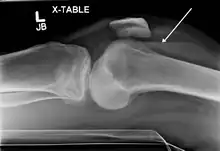

Lateral Tibial Plateau fracture XRay with Depression

• Type III: Focal depression of articular surface with no associated split.

This is a pure compression fracture of the lateral or central tibial plateau in which the articular surface of the tibial plateau is depressed and driven into the lateral tibial metaphysis by axial forces.3 A low energy injury, these fractures are more frequent in the 4th and 5th decades of life and individuals with osteoporotic changes in bone. They are extremely rare. Can be further divided into two subtypes: IIIA Compression Fracture of the lateral tibial plateau IIIB Compression Fracture of the central tibial plateau May result in joint instability.